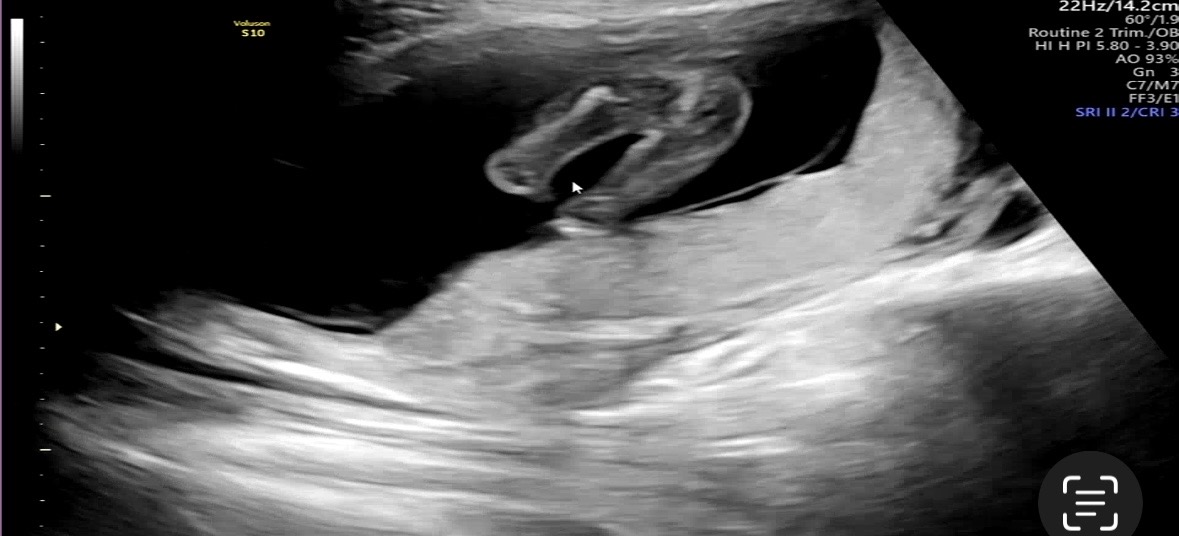

15주3일차 다리사이 봐주세요옹 !!

90퍼센트 딸 같다고 하시긴했는데 반전 없겠죠?? 12주엔 아들같다고 하셨어서 딸이라니 신기하기도하고 안 믿기기도 해서 딸맘님들이랑 초음파 똑같나용?